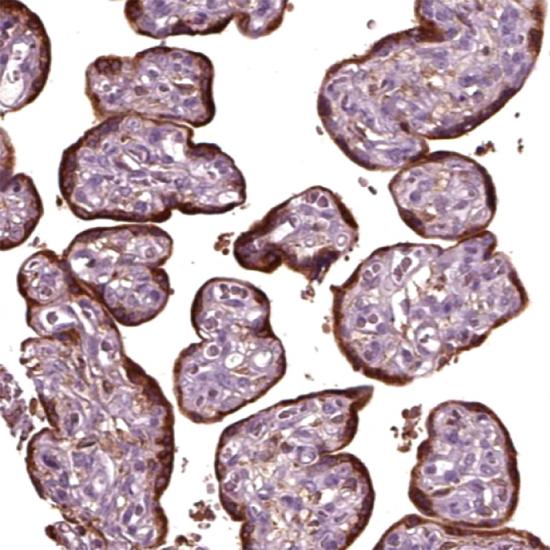

鼠抗人人糖蛋白激素α亞基(hCG-α)單克隆抗體

• 陽性部位:

細(xì)胞漿

• 陽性對(duì)照:

胎盤

人絨毛膜促性腺激素(HCG)是由胎盤的滋養(yǎng)層細(xì)胞分泌的一種糖蛋白,它是由α和β二聚體的糖蛋白組成。HCG-α在許多惡性腫瘤中存在表達(dá),可能與腫瘤的發(fā)生發(fā)展有關(guān)。